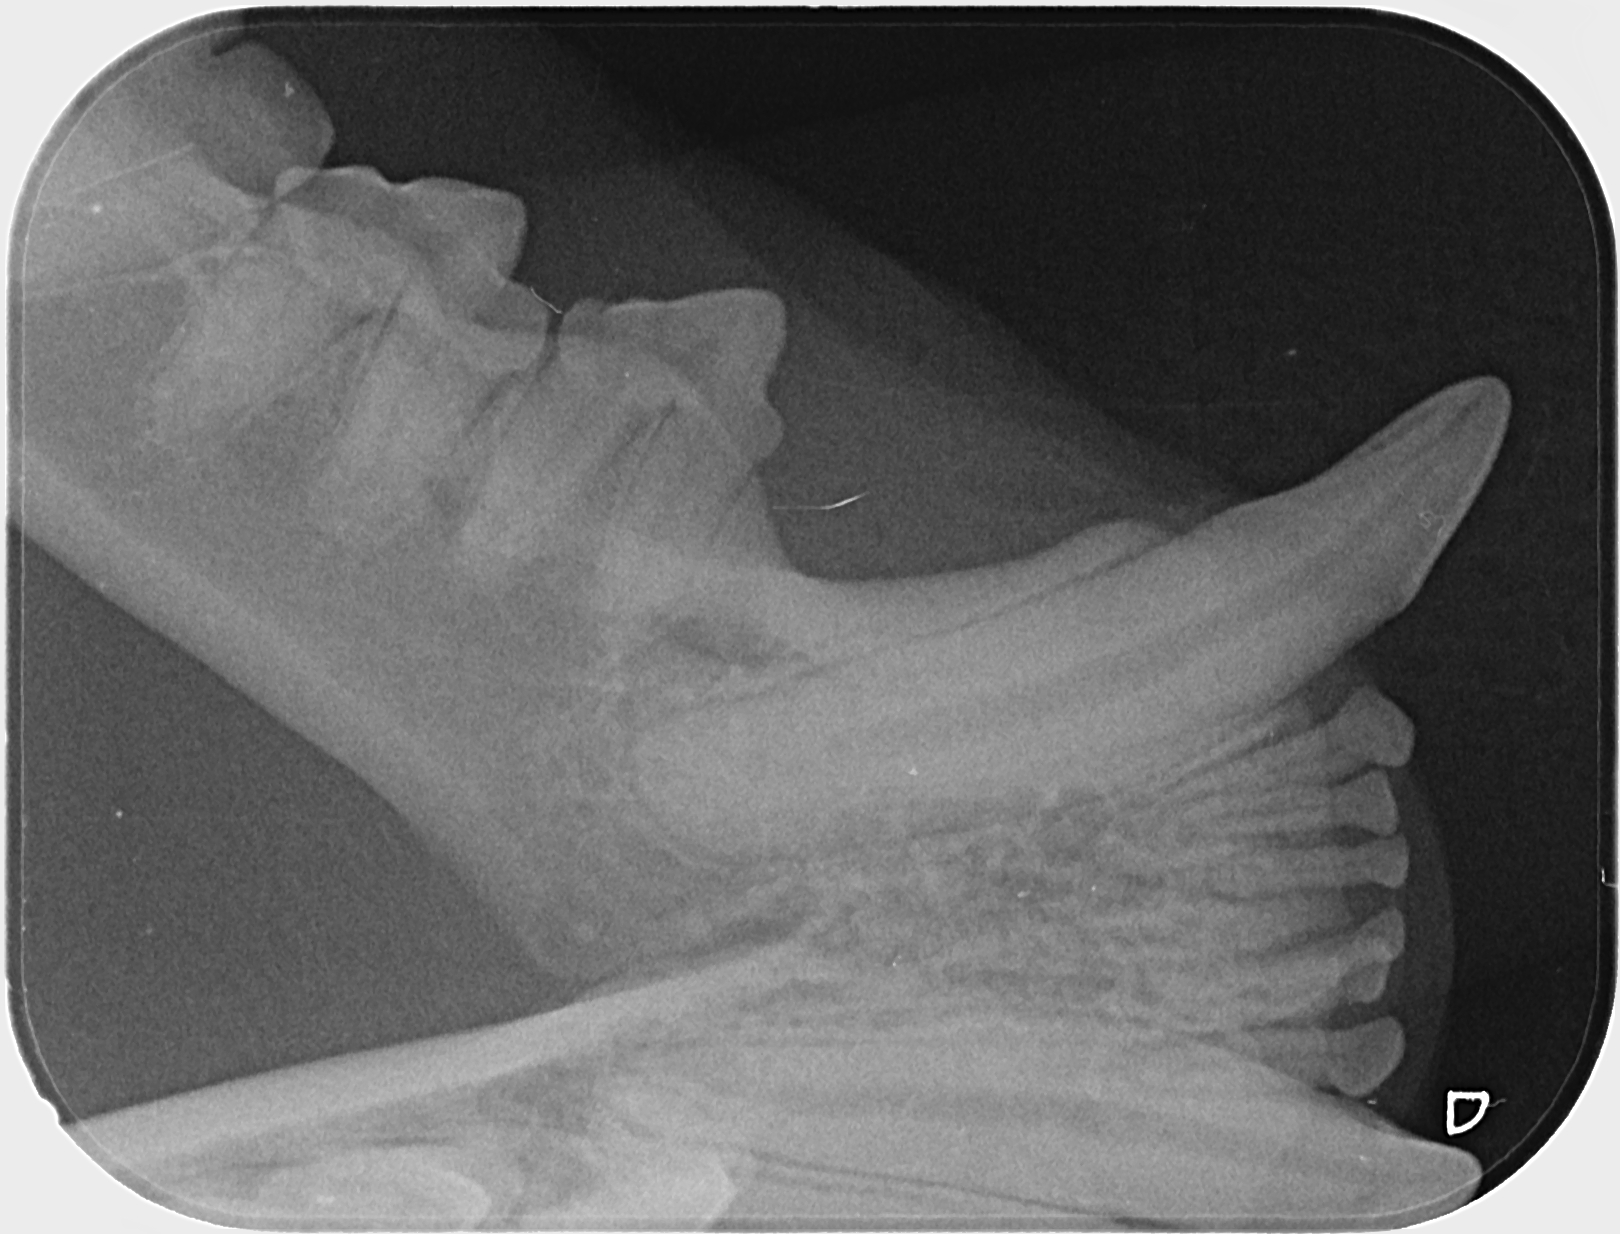

Kissan hampaat voivat näyttää päällisin puolin ihan hyvältä, mutta hampaiden juurissa voi olla piileviä ongelmia. Ainoa tapa selvittää, ovatko hampaat oikeasti kunnossa, on ottaa hammasröntgen.

IC Moggi Sikuri Sakari(Kilju) piipahti jo jonkin aikaaa sitten Amyvetissä hammahuollossa ja samassa kalusto pääsi kuviin. Tulos oli juuriaan myöten terveet hampaat. Hammaskiven poistoa pienesti ja ohjeeksi harjailla hampaita ahkerasti.

Ohessa muutama kuva malliksi.